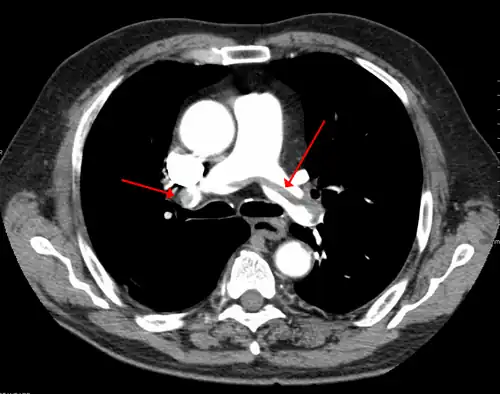

A CT image with red arrows indicating PE (grey) in the pulmonary arteries (white)

A pulmonary embolism (PE) occurs when a blood clot from a deep vein (a DVT) detaches from a vein (embolizes), travels through the right side of the heart, and becomes lodged as an embolus in a pulmonary artery that supplies deoxygenated blood to the lungs for oxygenation.[28] Up to one-fourth of PE cases are thought to result in sudden death.[12] When not fatal, PE can cause symptoms such as sudden onset shortness of breath or chest pain, coughing up blood (hemoptysis), and fainting (syncope).[29][30] The chest pain can be pleuritic (worsened by deep breaths)[29] and can vary based upon where the embolus is lodged in the lungs. An estimated 30–50% of those with PE have detectable DVT by compression ultrasound.[30]